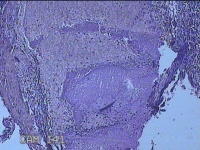

宫腔内容物

性别

女

年龄

39岁

临床诊断

异常子宫出血 重度贫血

一般病史

阴道流血20天,头晕乏力7天。

标本名称

大体所见

灰白暗红色不规则碎组织5.3x4.5x1.3cm一堆。

图1